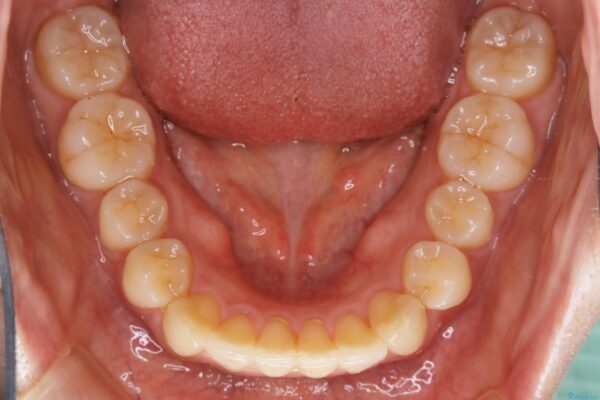

ディスキング(IPR)

歯のガタつきをとるためのスペース作りの方法の一つにディスキング(IPR)という方法があります。

歯と歯の間を一ケ所あたり最大0.5mmまでの範囲内で削ることで歯自体が少し小さくなり、それにより作られるスペースを数ヶ所分合わせることで合計で数mmの大きなスペースが作れるという方法です。

当院ではなるべく歯の機能や見た目に影響の出ないよう、作業時に拡大鏡の使用や削るタイミングの微調整を行っています。